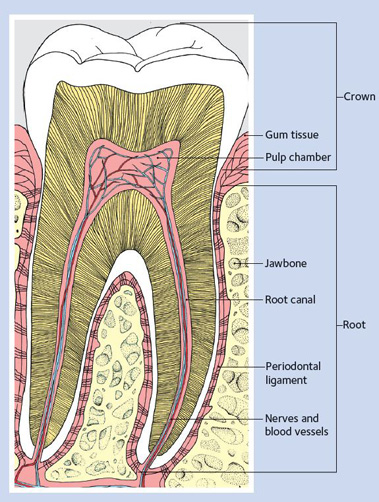

The pulp is soft tissue inside the tooth that contains blood vessels and nerves. When the pulp becomes inflamed or infected, treatment is needed. The most common causes of pulp inflammation or infection are a cracked or chipped tooth, a deep cavity or filling, or other serious injury to the tooth. All of these can allow bacteria to enter the pulp.

Diagram of a Healthy Tooth